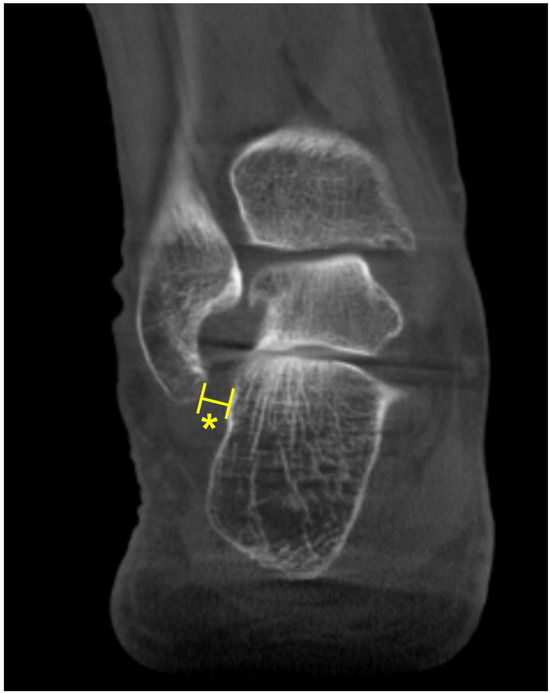

The talonavicular coverage angle is also used in WBCT as an indicator to assess midfoot abduction [36]. In fact, a new classification system for PCFD includes sinus tarsi impingement as one of the findings of midfoot abduction. Sinus tarsi impingement, which commonly causes lateral hindfoot pain, is caused by bony contact between the talus and calcaneus and should be addressed when establishing a therapeutic strategy in PCFD [42]. Because of superimposition effects, however, sinus tarsi impingement is difficult to identify using conventional radiographs. Instead, WBCT allows for the identification of bony impingement in a physiological standing position. Kim et al. devised a novel method to measure the talocalcaneal distance, which features realignment of the coronal and sagittal planes to directly trace the inferior border of the lateral process of the talus [43] (Figure 8). The inferior border of the lateral process of the talus is chosen to reconstruct the coronal reference plane because it is a constant anatomical landmark to obtain minimal talocalcaneal distance. Using this method, the authors investigated the correlation of talocalcaneal distance narrowing with common radiographic parameters on standard weight-bearing radiographs. They observed that talocalcaneal narrowing correlated most with talonavicular coverage, with a cutoff value of 41.2 degrees. Andres et al. conducted a comparative study to identify whether there is an association between WBCT-based measurements and MRI findings [44]. They found that MRI findings overestimate the presence of bony sinus tarsi impingement in approximately 42% of the included population and concluded that WBCT would be a better diagnostic option to detect bony impingement in PCFD.

Figure 8.

Talocalcaneal distance. (A) Using the sagittal view for reference, the most inferior point of the lateral process is identified. (B) At this point, the narrowest distance between the inferior border and the calcaneal floor is measured in the selected coronal slice (Asterisk).